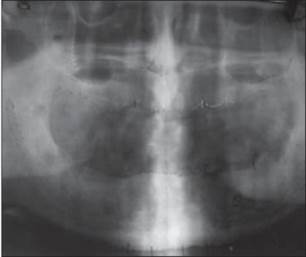

El tratamiento del edentulismo parcial y total con implantes dentales se ha convertido en un procedimiento predecible para la mayoría de los pacientes y se espera que desempeñe un papel importante en la rehabilitación oral. La colocación quirúrgica de implantes dentales es un tratamiento bien documentado para el edentulismo (Adell et al., 1990). Las tasas de éxito del tratamiento son altas y las complicaciones postoperatorias fueron relativamente modestas. El tratamiento exitoso de implantes implica la osteointegración de implantes que se colocan en posiciones ideales para la fabricación de una prótesis dental (Jacobs et al., 1999). La evaluación clínica periódica del accesorio del implante, la prótesis y el tejido circundante es crítica para el éxito clínico. En el presente caso, el paciente fue llamado por cada 3, 6 y 12 meses, se realizó la extracción profesional de depósitos supragingivales y subgingivales de forma regular [Figura 10] .

Figura 10: Radiografía postoperatoria de seis meses